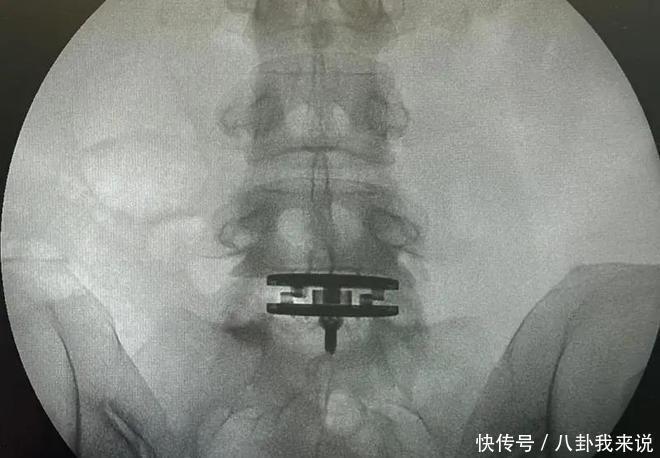

陈奕迅才摔伤休克「老婆也动刀」!她患1症超难受:打喷嚏就剧痛

椎间盘

腰间盘突出

腰椎间盘突出

腰椎间盘突出症

微创